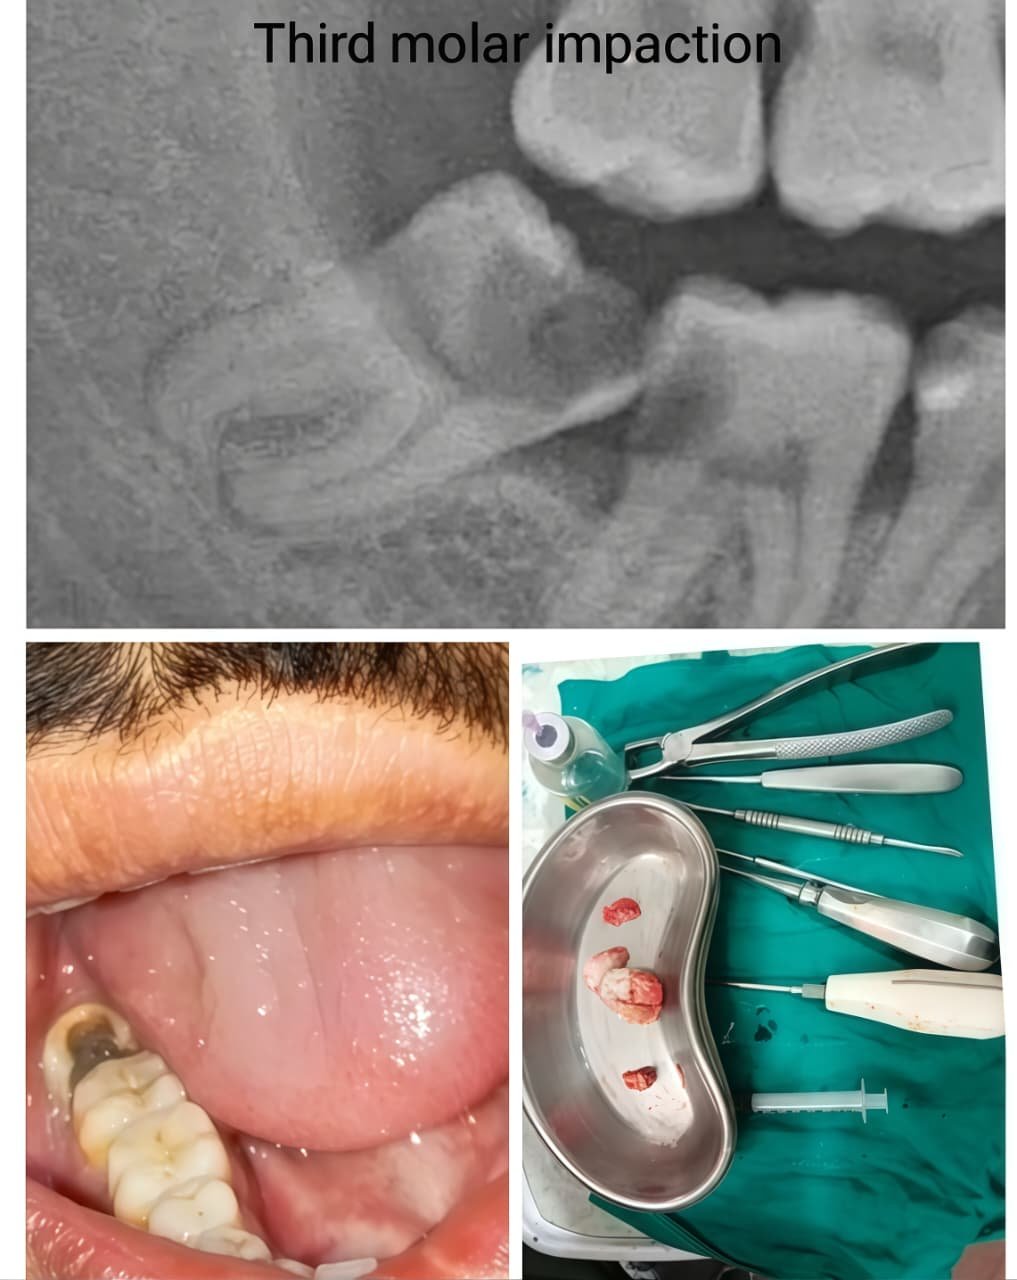

Before & After Case Studies

Our patients experience life-changing transformations. These cases demonstrate our commitment to exceptional results. Each success story represents our dedication to precision and aesthetic excellence.